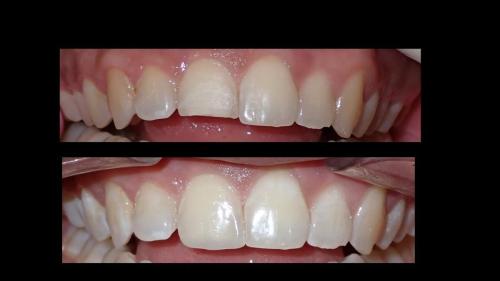

Galería de Sonrisas

large-Resultados sin que se note ortodoncia

large-Resultados con balance

large-Fractura con resina

large-Fractura